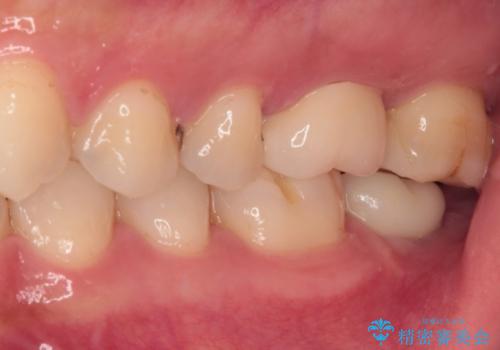

強い咬合力を負担する第一大臼歯であるため、根管治療後は速やかにオールセラミッククラウンにて補綴治療を行うこととしました。